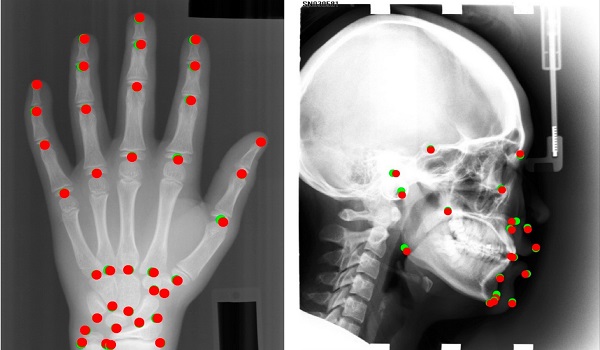

در اين بخش نگاه کاربردي به علم پردازش تصوير، بينايي ماشين و پردازش ويدئو خواهيم داشت